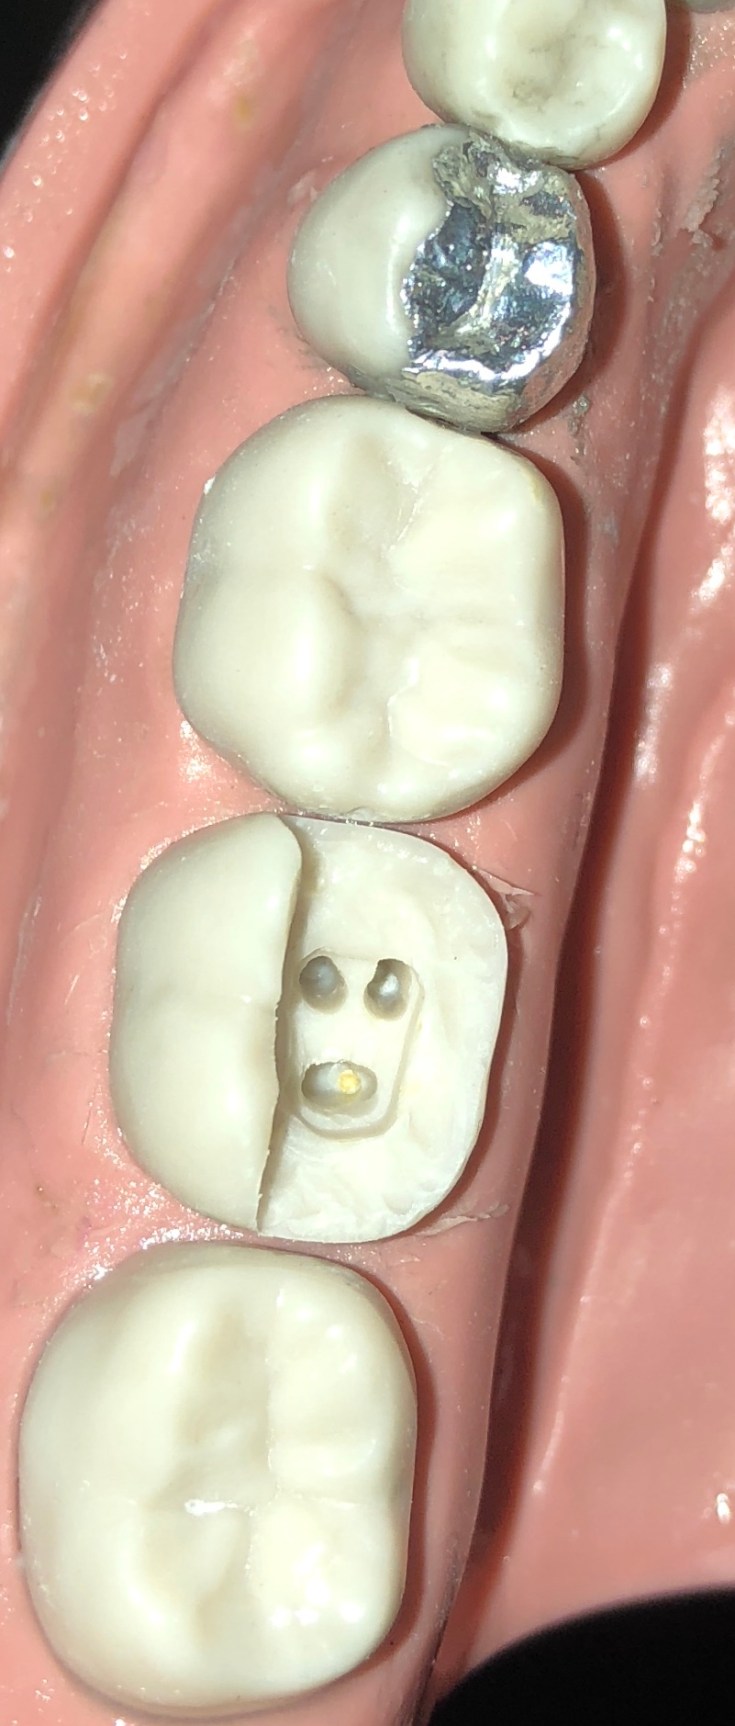

Module 5 of the Operative Dentistry course considered restoration of Endodontically treated teeth using bonded amalgam restorations. Teeth LL4 and LL7 were prepared with MODL cavities to simulate to extent of tooth tissue loss often encountered in root filled teeth. As amalgam does not bond to enamel or dentine it is important to incorporate appropriate resistance and retention form in cavity design. Grooves and amalgapin preparations were incorporated into the dentine of LL4 and a nayar core was planned in the LL7 to utilised the pulp space and coronal portion of the root canal system for retention. The cavities were isolated with an annealed automatrix which was adaptation marginally and secured with wedges from the lingual surface. The enamel and dentine were etched and bonded and panavia V5 applies to base of the cavities. Tytin amalgam was packed and carved with fissure pattern and cusp shapes incorporated. The automatrix was removed and final fissure and cusp carving performed with burnishing and the use of green and brown stones to polish. A bristle brush was useful to achieve a final high polish. Equally the restoration could be sandblasted if a matte finish was preferred. An indirect restoration may be later considered particulary in root filled teeth where protection from fracture is considered appropriate. Although composite rsi restoration may offer a more aesthetic and preferred option to restore with – especially with future phase down of amalgam use planned – amlagam is still a very useful material in scenarios where moisture control is suboptimal and continues to provide predicable and robust outcomes backed up with long term success rates.